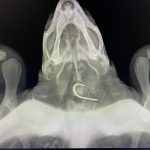

-Tu je kornjača pregledana i obavljeno je rendgensko snimanje koje je pokazalo prisutnost udice u jednjaku.

Na svu sreću nije bilo potrebe za operativnim zahvatom već je udica odstranjena manualno. Jednom kada je procijenjeno da kornjača može podnijeti dulji put veterinar ju je osobno doveo u Centar gdje će se nastaviti njezin oporavak – rekli su iz akvarija.